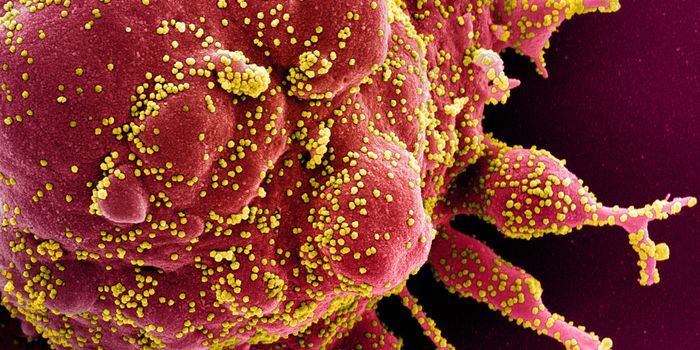

MAY 03, 2020Genetics & GenomicsThe origin of SARS-CoV-2, the pandemic virus that causes COVID-19, has become politicized as leaders seek to place blame ...

JUL 06, 2020MicrobiologyThe pandemic coronavirus has caused a wide range of different symptoms, and as time goes on, we may find that it can hav ...

JUL 05, 2020Cell & Molecular BiologyThe pandemic virus SARS-CoV-2 enters the body through the respiratory system to cause the illness COVID-19. But we know ...

JUN 29, 2020MicrobiologyVaccines that contain live attenuated viruses may be giving people some protection from serious cases of COVID-19 that i ...

FEB 22, 2021MicrobiologyReporting in Science, researchers have created an antiviral nasal spray that could help us get the COVID-19 pandemic und ...

SEP 01, 2021MicrobiologyIt's been generally assumed that people who get infected with SARS-COV-2 will develop antibodies to the virus, which cau ...

MAR 18, 2020MicrobiologySARS-CoV-2 is a coronavirus that causes an illness called COVID-19. There are now well over 210,000 confirmed cases worl ...